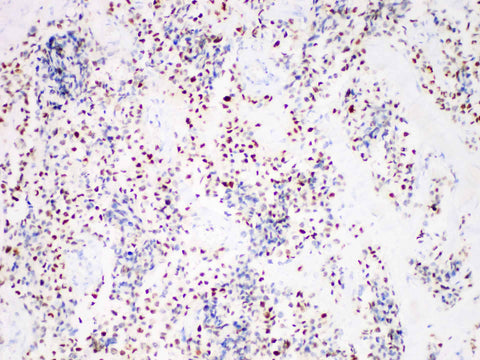

Myogenin Monoclonal Antibody Stored at 2~8°C

Applications IHC-P

Cellular Localization nucleus

Tissue Specificity Rhabdomyosarcoma

Myogenin, a member of the myogenic regulatory factor family, is a transcription factor essential for skeletal muscle cell genesis. Staining was also found in myoblasts of human fetal limbs, whereas no reactivity was found in adult skeletal muscle. Myogenin staining has been observed in the vast majority of rhabdomyosarcomas and wilms' tumors, and no activity has been observed in Ewing sarcoma/peripheral primitive neuroectodermal tumors or neuroblastoma. It is now used to label striated muscle cells and tumors from which they originate.